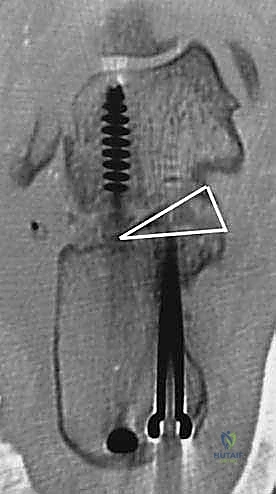

- دمج المفصل تحت الكاحل (Subtalar Arthrodesis):

في الغالبية العظمى من حالات سوء الالتئام، يكون المفصل تحت الكاحل قد تدمر تماماً بسبب الخشونة والاحتكاك. الحل الجذري والنهائي للألم هنا هو "دمج" أو "تثبيت" هذا المفصل. يقوم الدكتور هطيف بتنظيف الغضاريف التالفة بالكامل، ووضع العظام في وضعها التشريحي الصحيح، ثم تثبيتها باستخدام براغي معدنية قوية جداً (Screws) لتلتحم وتصبح عظمة واحدة صلبة خالية من الألم.